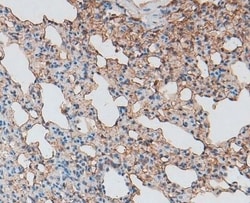

Invitrogen™ Glypican 3 Polyclonal Antibody

Antibody detects endogenous levels of total GPC3.

| Applications | Immunohistochemistry (Paraffin), Western Blot, Immunocytochemistry, Western Blot |